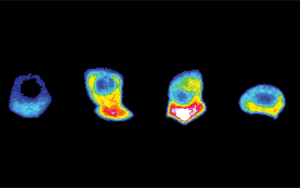

Cell:改善細胞反應與混合免疫

華盛頓大學醫學院(University of Washington School of Medicine)的研究人員表示,與只有疫苗保護的人相比,在接種疫苗之前感染了SARS-CoV-2的人會產生更具體的免疫反應,并產生更廣泛的抗體反應。